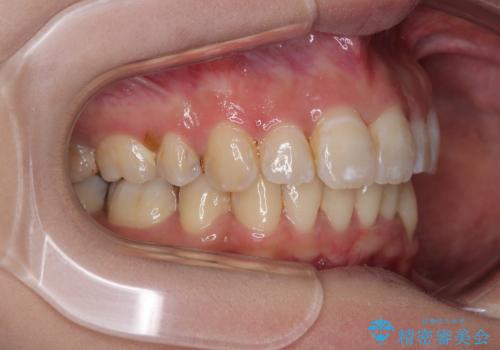

どこまで口元の突出感を改善できるのか不安でしたが、舌のトレーニングをしっかりと行ってくださり、我々も驚くほど劇的に改善することができました。